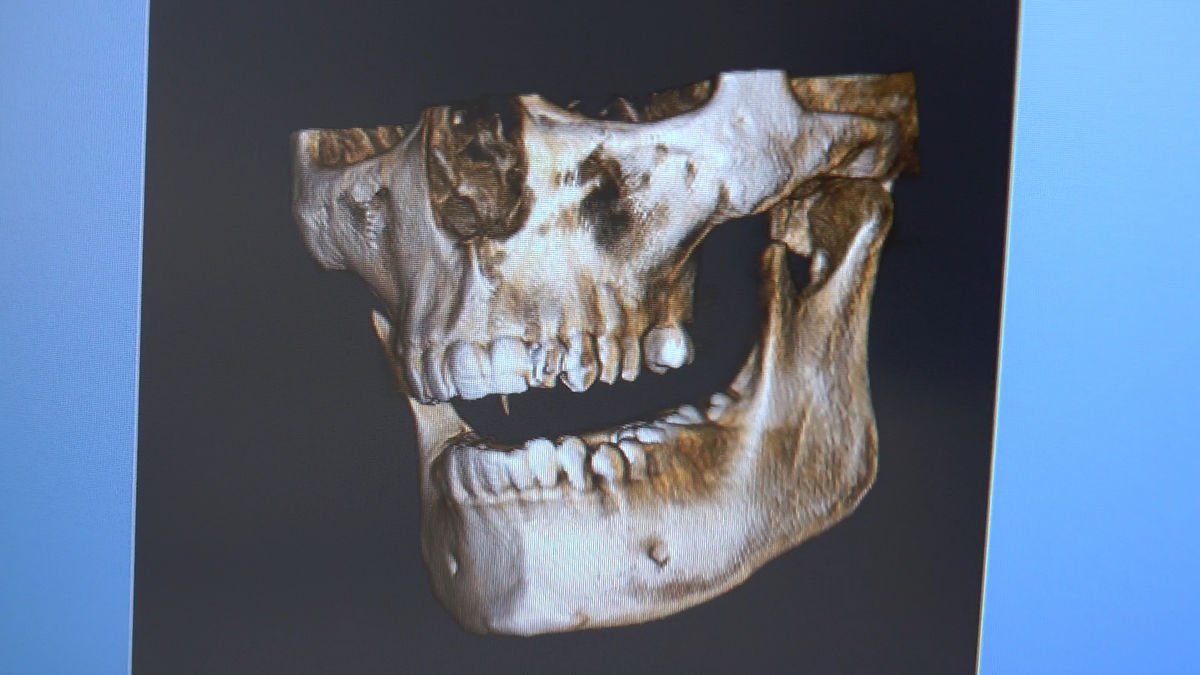

Practiculum Implantologii – Sezon VI, sesja 3, część 1